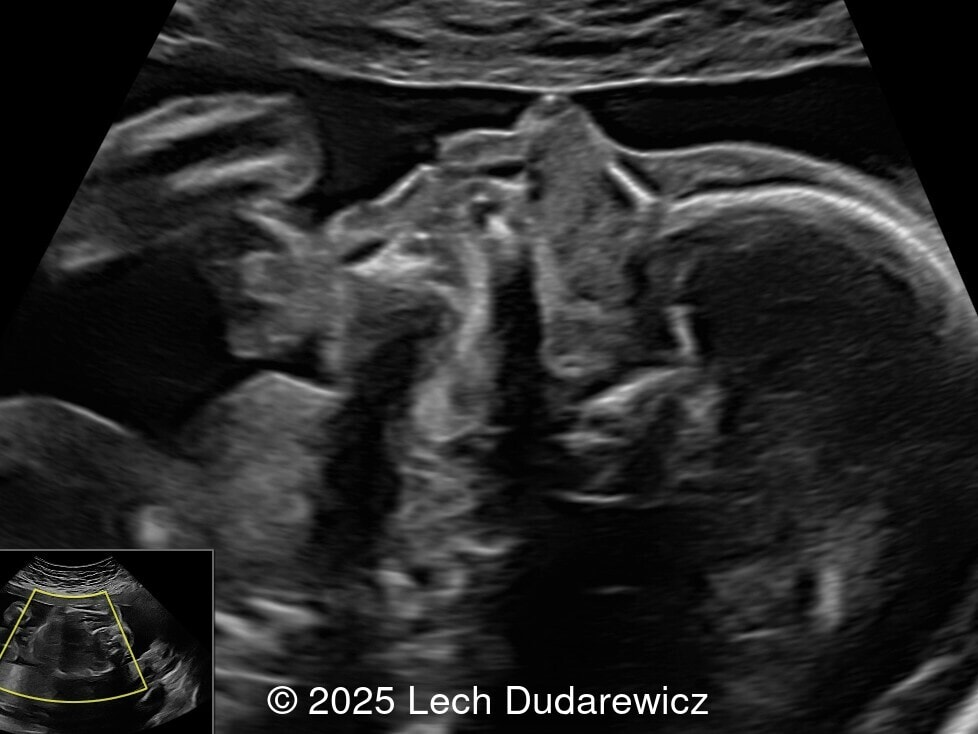

Image 2

Ultrasound images demonstrated a symmetrically enlarged thyroid gland that was isoechoic to slightly hyperechoic relative to the surrounding tissues. Color Doppler revealed peripheral hypervascularization of the thyroid, known as the “peripheral vascular rim sign”. No internal parenchymal hyperperfusion was noted. Amniotic fluid volume was within normal limits and no structural anomalies were observed in the remainder of the scan.

Prenatal ultrasound is the preferred method of screening for head and neck masses. The first ultrasound diagnosis of a fetal goiter was made by Weiner et al. in 1980 [11], and since then several cases have been published, mostly isolated or small series [12,13]. Ultrasound can accurately assess the size, location, internal blood supply, and growth of the fetal goiter, as well as evaluating its effects on neighboring structures and amniotic fluid volume. Key sonographic findings include a homogeneous, echogenic, symmetric mass in the anterior portion of the fetal neck corresponding to the thyroid enlargement (measurements above the 95th percentile for gestational age), polyhydramnios (not always present), and abnormal fetal neck contour [1]. On color Doppler evaluation, peripheral hyperperfusion ("peripheral vascular rim sign") supports the diagnosis of hypothyroidism with a hypertrophic but inactive thyroid gland. Diffuse parenchymal hyperperfusion (“thyroid inferno”), due to an overactive thyroid gland, is expected in hyperthyroidism [14,15]. Three-dimensional ultrasound may facilitate the parent’s understanding of the fetal goiter [16] and magnetic resonance imaging (MRI) can be useful for evaluating the compression and patency of the trachea and esophagus [17].